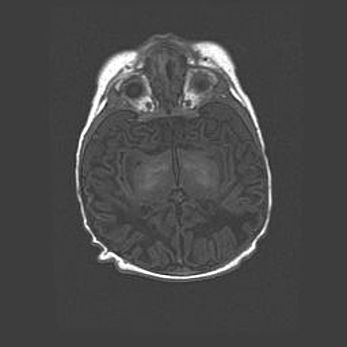

Лейкомаляция с кистозно-глиозной дегенерацией головного мозга.

Возраст: 2 месяца 25 дней

Вес: 6400 г

Окружность головы: 40 см

Срок гестации: 41 неделя

Лейкомаляцию относят к ишемически-гипоксическим повреждениям головного мозга, диагностируемым у новорожденных. При лейкомаляции в головном мозге обнаруживают очаги некроза, возникшие после тяжелой гипоксии и нарушения кровотока. В процессе морфогенеза очаги проходят три стадии: 1) развития некроза, 2) резорбции и 3) формирования глиозного рубца или кисты. Перивентрикулярная лейкомаляция (ПЛ) встречается примерно в 12% случаев среди новорожденных, обычно – у недоношенных детей, причем, частота ее зависит от массы, с которой младенец появился на свет. Наибольшее число малышей страдает лейкомаляцией, если масса при рождении 1500-2500 г.